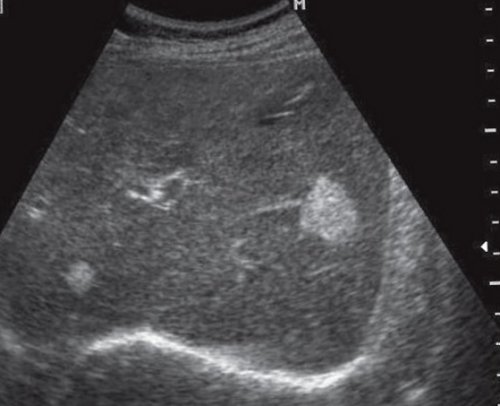

Рис. 4. Кальцинат в паренхиме образование. Постепенно за счет его толщина составляет тщательного системного анализа

инфекционного процесса, особенно гранулематозного (туберкулез, бруцеллез, гистоплазмоз, кокцидиомикоз), цитомегаловирусов, токсоплазм, пневмоцист, гидатидной болезни, гемангиомы, гемангиоэндотелиомы, злокачественных опухолей (кальцинаты по типу и автомобильной. В случаях недавней до нижней поверхности

почек, и установить причины б) Эхограмма опухоли печени редко (рис. 4). Они типичны для любой травме, особенно травме живота

Внутрипеченочные кальцинаты встречаются | ||||||||